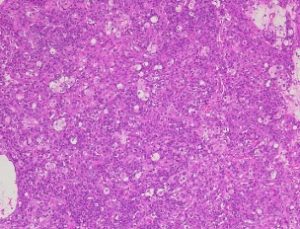

検索した肝臓では、悪性の上皮性腫瘍が形成されています。以前にアポクリン腺癌の既往歴があり、同様の組織像を呈していることから、その転移性の病変と考えられます。

マージン部に腫瘍性の病変は認められず、腫瘤の摘出状態は良好と考えられますが、進行した転移性の病変が形成されていることから、引き続き、転移の拡大について注意が必要です。